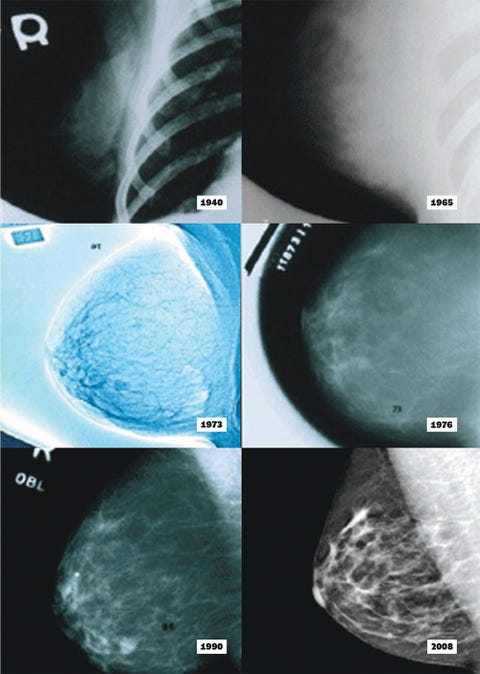

For decades, mammograms have been deemed an essential rite of passage for women over 40—a mandate similar to that of a driver’s license. The logic is straightforward: early detection saves lives. But does it really? Recent studies indicate that not all women may benefit equally from this ubiquitous procedure. The uncomfortable truth surfaces that mammography disproportionately affects women in different age brackets and varying health conditions.

Enter 3-D mammography, a breakthrough that touts a myriad of advantages over its 2-D predecessor. This new technology claims to reduce false positives and facilitate earlier detection of breast malignancies. However, let’s not rush into the hype. Is this really an advancement, or are we simply adding a more intricate layer to an already convoluted process?